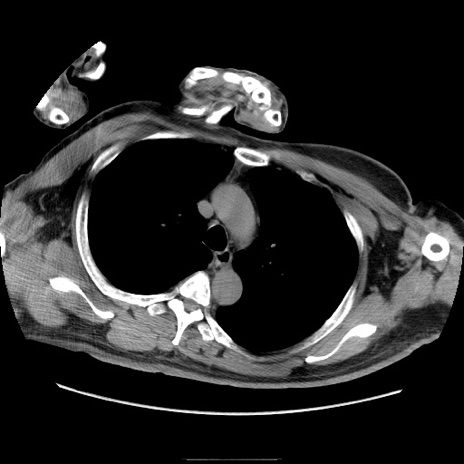

症例22(横断像)

【症例】50歳代男性

【主訴】腹痛

【現病歴】AVMからの被殻出血のため回復期リハ病棟入院中。 本日午後3時頃急に下腹部痛が出現した。

【既往歴】AVM、被殻出血、虫垂炎、高血圧

【身体所見】意識晴明、左半身不全麻痺、会話の理解は良好、36.5°C、腹部:膨隆、全体に板状硬、下腹部正中に圧痛点あり、反跳痛-、筋性防御不明、右下腹部にope scar

【データ】WBC 9400、CRP 0.06